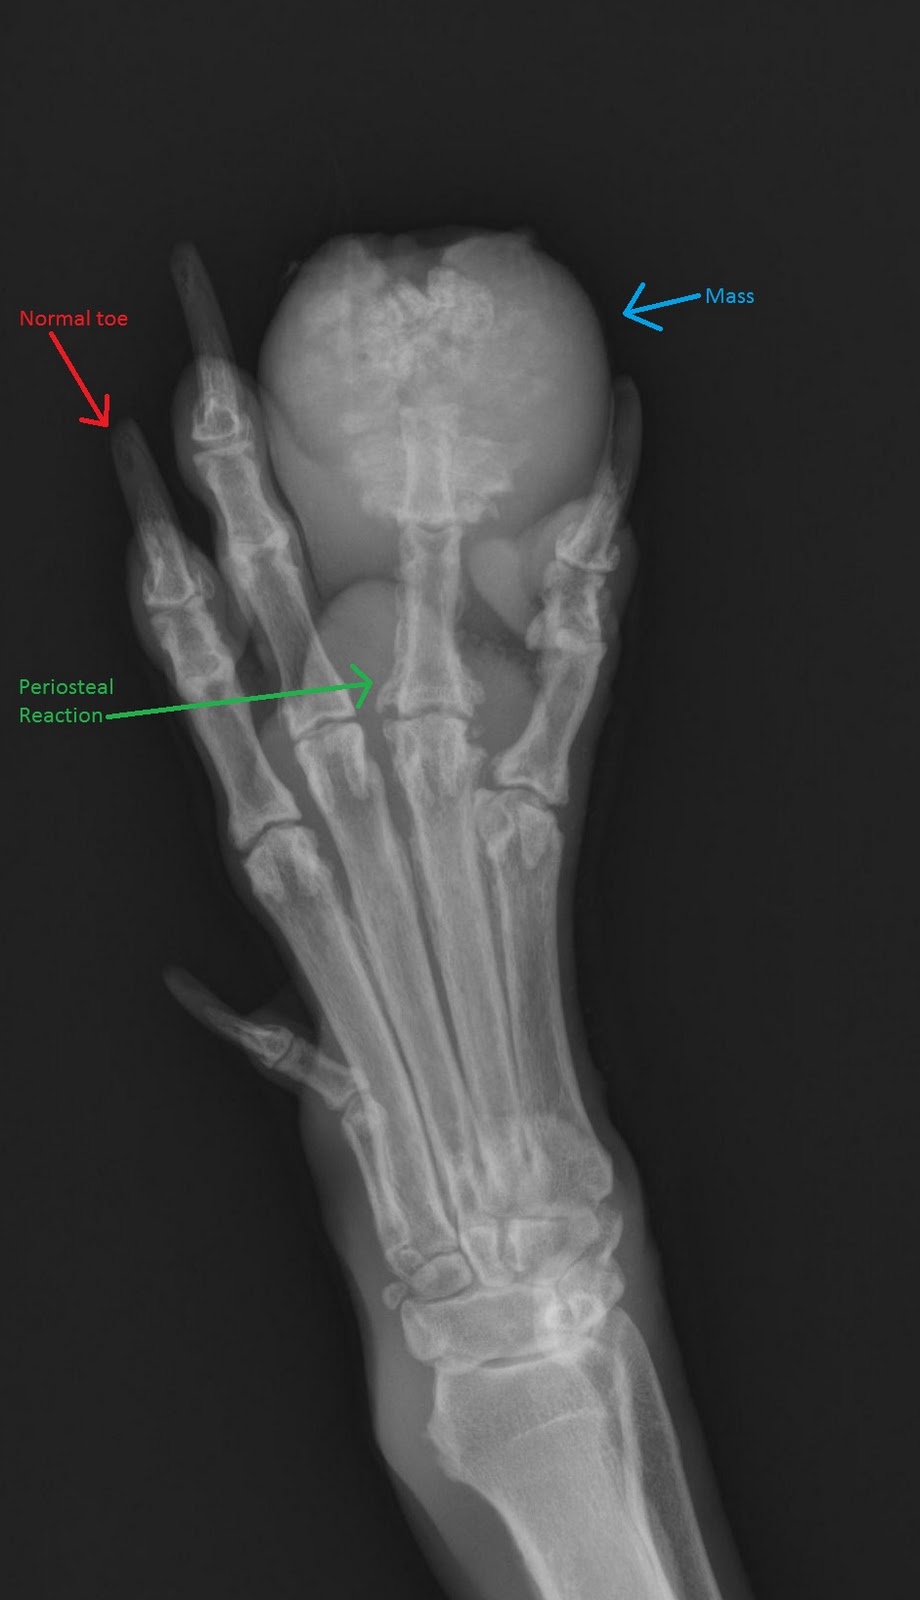

Even with bone cancers comprising less than 1% of all types of cancers, the american cancer society still estimates that 1,720 deaths from 3,200 new cases of bone cancer will occur in 2020. With such shocking statistics, keeping an eye out for possible symptoms of bone cancer is an absolute necessity. When a bone tumor grows, it presses on healthy bone tissue and can destroy it, which causes the following symptoms: What bone metastasis looks like. But some types of cancer are particularly likely to spread to bone, including breast cancer and prostate cancer. People with bone sarcoma may experience the following symptoms or signs. Whether primary or metastatic, cancer in the bones may present with symptoms such as pain, swelling, and/or a sudden intense pain from a pathologic fracture —a fracture that occurs in a bone that has been weakened by the presence of a tumor. Bone tumors of the foot are rare, comprising only three to six percent of all bone tumors, and are benign in 75 to 85 percent of cases (sarcoma, 2013).

Lumps, swellings, fractures, joint tenderness and pain are some common symptoms of bone cancer in ankle and foot. Bone metastasis occurs when cancer cells spread from their original site to a bone. There are different types of primary bone cancers, like osteosarcoma and ewing sarcoma. See foot cancer stock video clips. Bone cancer can affect any bone, but most cases develop in the long bones of the legs or upper arms. Ct scans are usually used to help form an initial bone cancer diagnosis and to see whether the cancer. Osteosarcoma, the most common bone cancer, usually happens to people ages 10 to 30 and most often starts in the arms, legs, or pelvis. Foot or toe cancer (digital and soft tissue cancer), which can include squamous cell carcinoma, melanoma, osteosarcoma, mast cell tumor, and malignant soft tissue sarcoma is common in dogs. The bone pain is described as aching, throbbing, stabbing, and excruciating. Bone metastasis can occur in any bone but more commonly occurs in the spine, pelvis. Cancer in the bones of the spine can press on the nerves coming out of the spinal cord. Bone cancer is a malignant form of cancer that begins in the bone and destroys healthy bone cells. Primary bone tumors can be either benign or malignant.

This uncommon kind of cancer affects both adults and children. But some types of cancer are particularly likely to spread to bone, including breast cancer and prostate cancer. They work to destroy the tumor or slow down the growth of cancer cells. _____american cancer society cancer.org | 1.800.227.2345 including: Caused by a local inflammation such as arthritis or. It may resemble a plantar's wart or a foot ulcer, and it may feel scaly. Bone cancer can begin in any bone in the body, but it most commonly affects the pelvis or the long bones in the arms and legs. A type of bone cancer called osteosarcoma is the most common type of primary bone cancer in dogs, accounting for over 95% of all bone tumors. Cancer in bone can cause intermittent or progressively severe localized bone pain where the cancer is in the bone. Lumps, swellings, fractures, joint tenderness and pain are some common symptoms of bone cancer in ankle and foot. The bone may look ragged, or it may appear to have a hole in it. Sometimes, people with bone sarcoma do not have any of these changes. Bone cancer, like many other types of cancer, can sometimes cause weight loss and fatigue.

Local treatments focus on just the bone or bones where the cancer spread. Lumps, swellings, fractures, joint tenderness and pain are some common symptoms of bone cancer in ankle and foot. If detected in the early stages, foot cancer can be treated effectively. Bone tumors of the foot are rare, comprising only three to six percent of all bone tumors, and are benign in 75 to 85 percent of cases (sarcoma, 2013). _____american cancer society cancer.org | 1.800.227.2345 including: Cancer in bone can cause intermittent or progressively severe localized bone pain where the cancer is in the bone. A bone spur appears as a tiny, pointed growth on a bone, according to medicinenet. What does a bone spur look like? Primary bone tumors are relatively rare after the fourth decade of life and less frequent as compared to secondary bone tumors. In fact, noncancerous bone tumors are much more common than cancerous ones. It may resemble a plantar's wart or a foot ulcer, and it may feel scaly. Nearly all types of cancer can spread (metastasize) to the bones. Bone cancer, like many other types of cancer, can sometimes cause weight loss and fatigue.